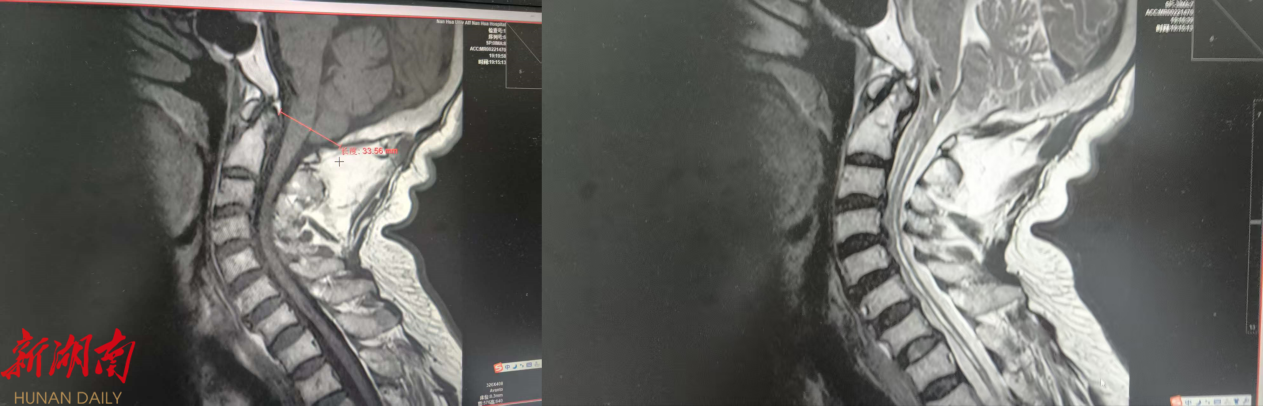

△小脑扁桃体下疝畸形伴颈髓空洞影像

近日,患者谭某某,因“四肢麻木无力3年”,辗转多家外院治疗效果不佳,后转入南华大学附属南华医院神经内科。经系统检查,提示病变位于颈髓,颈椎磁共振显示长节段异常信号,初步考虑为脊髓空洞伴小脑扁桃体下疝。神经外科陈锐博士会诊后,患者转入神经外科接受进一步治疗。

转入神经外科后,全科医师经过讨论及全面评估,诊断患者为“小脑扁桃体下疝畸形伴颈髓空洞”,且具备明确的手术指征。科室主任邹钦及陈锐博士治疗团队决定为患者实施手术治疗。传统手术方式需切除部分小脑扁桃体,术后患者恢复时间长,术后反应重,头昏不适感明显。手术组经过严密分析患者影像学特点,决定另辟蹊径,保留患者小脑扁桃体,在严密神经电生理监测下,为患者行“微创后颅窝减压术+小脑扁桃体松解术”。手术十分顺利,患者肢体麻木症状完全消失,无其他特殊不适,术后顺利拆线出院。